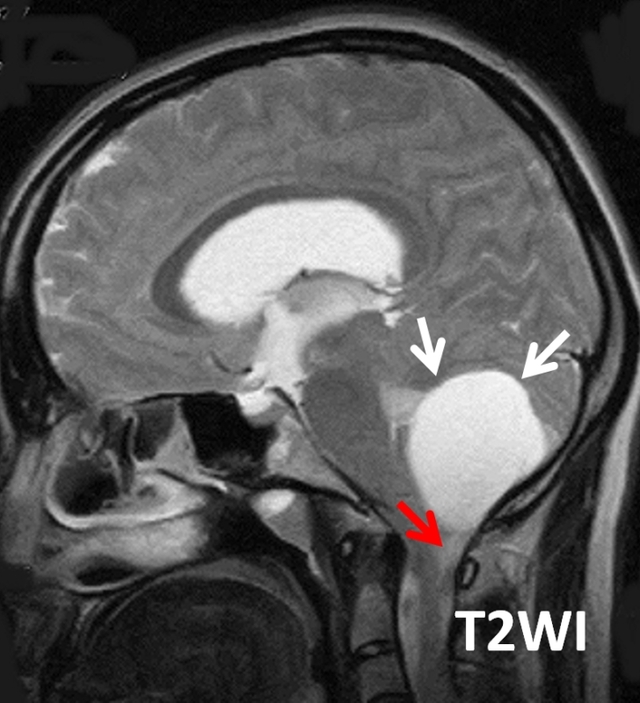

患者女性,29岁,头痛、视物模糊和共济失调。

答案:A. Blake囊肿

Blake囊肿是一种后颅窝的小蛛网膜囊肿畸形,被认为是继发于第四脑室正中孔形成障碍的Blake小袋退化失败所致髓帆向小脑延髓池的囊性扩张。

Blake囊肿经典的影像学表现有后颅窝小脑蚓部(图中黄色箭头)后下方可见一装满脑脊液的囊肿(图中白色箭头),该囊肿后方与小脑延髓池(图中红色箭头)分离。该病例中未见小脑蚓部发育异常,而Dandy-Walker综合征这常伴小脑蚓部发育不全。